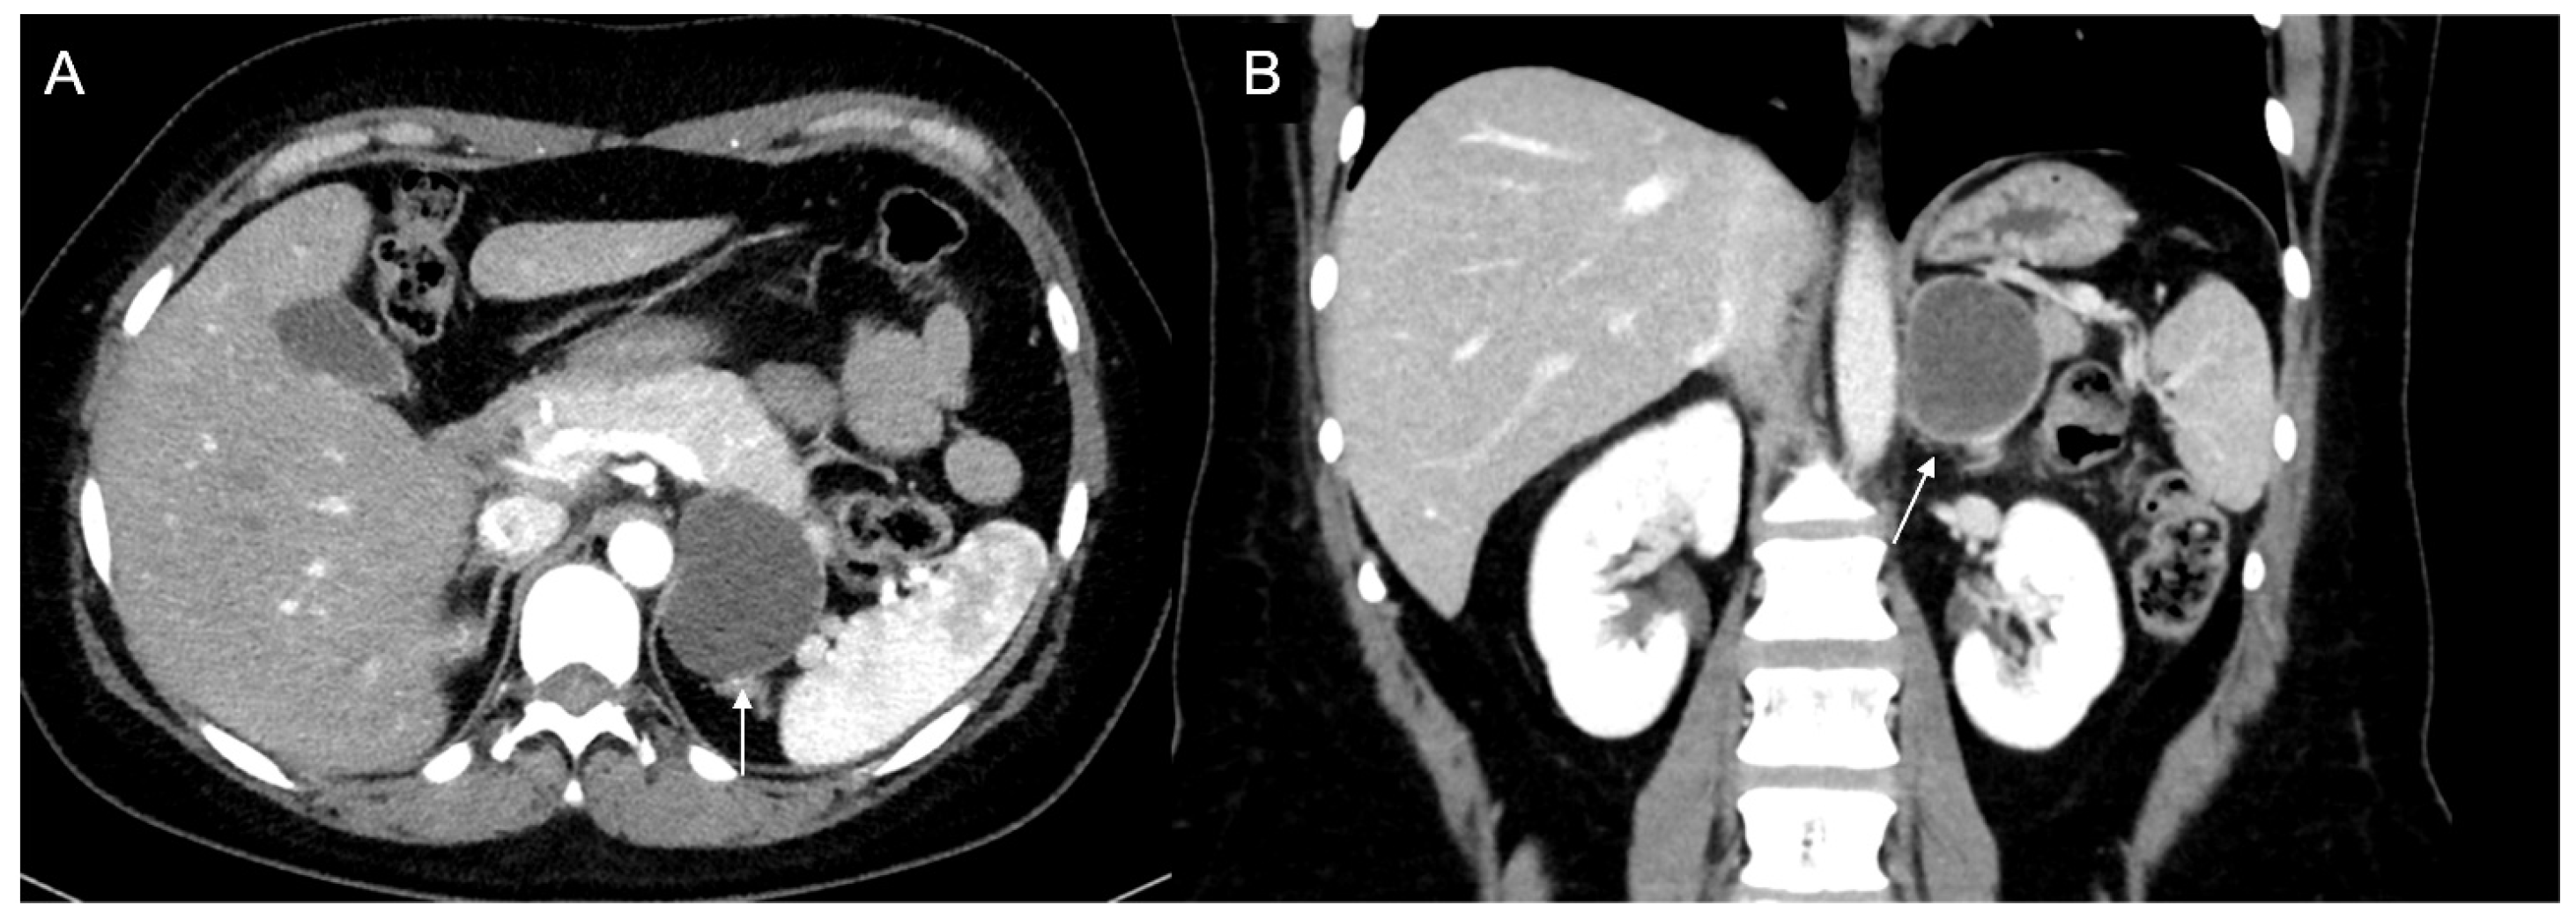

Figure 14.

Axial unenhanced (a), arterial (b), and coronal venous (c) CT phases show a lung carcinoid metastasis (arrow) of the left adrenal gland. Additional hypervascular metastasis can be seen in the liver, particularly in the arterial phase.